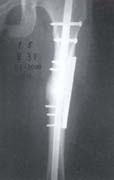

En los otros dos casos el acortamiento se debía a la fractura del fémur, en un caso el acortamiento era de 4.0 cm la fractura fue producida por arma de fuego con gran conminución y había sido tratada inicialmente con un clavo de Kunstcher, sin obtener consolidación, posteriormente se extrajo el clavo de Kunstcher y se estabilizó la fractura con un clavo bloqueado proximal y distalmente, injertos óseos, pero la fractura tampoco consolidó, razón por la cual se retiraron los tornillos de bloqueo distal y se colocó una placa como soporte del clavo y nuevos injertos óseos obteniéndose la consolidación como se muestra en la figura 2.

* Figura 2 A-C. Fractura de fémur tratada con clavo bloqueado no consolidada. Resultado de consolidación al colocar placa e injertos óseos.